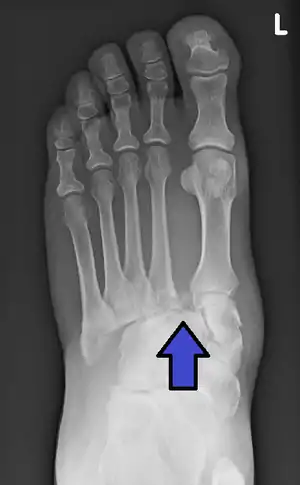

Lisfranc fracture (marked by the oval). This case also has fractures of the distal second (marked by the arrow), third, and fourth metatarsal bones.

In a high energy injury to the midfoot, such as a fall from a height or a motor vehicle accident, the diagnosis of a Lisfranc injury should, in theory at least, pose less of a challenge. There will be deformity of the midfoot and X-ray abnormalities should be obvious. Further, the nature of the injury will create heightened clinical suspicion and there may even be disruption of the overlying skin and compromise of the blood supply. Typical X-ray findings would include a gap between the base of the first and second toes.[10] The diagnosis becomes more challenging in the case of low energy incidents, such as might occur with a twisting injury on the racquetball court, or when an American Football lineman is forced back upon a foot that is already in a fully plantar flexed position. Then, there may only be complaint of inability to bear weight and some mild swelling of the forefoot or midfoot. Bruising of the arch has been described as diagnostic in these circumstances but may well be absent.[11] Typically, conventional radiography of the foot is utilized with standard non-weight bearing views, supplemented by weight bearing views which may demonstrate widening of the interval between the first and second toes, if the initial views fail to show abnormality. Unfortunately, radiographs in such circumstances have a sensitivity of 50% when non-weight bearing and 85% when weight bearing, meaning that they will appear normal in 15% of cases where a Lisfranc injury actually exists.[12] In the case of apparently normal x-rays, if clinical suspicion remains, advanced imaging such as magnetic resonance imaging (MRI) or computed tomography (CT scan) is a logical next step.[13]